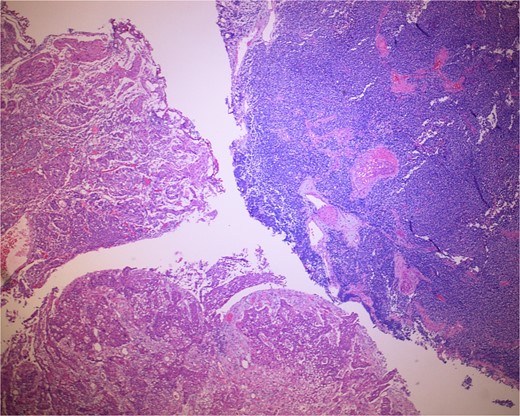

Low-power view of the neoplasm shows urothelial carcinoma on the left and neuroendocrine carcinoma on the right of the image.

The gross specimen consisted of multiple particles of gray friable tissue, aggregating to 58 g, 8 × 8 × 4 cm in greatest dimensions. Representative sections were submitted for histological processing and subsequent microscopic study in 12 cassettes. Histopathologic examination of the curated bladder mass revealed sheets of high-grade malignant urothelial carcinoma with adjacent areas of neuroendocrine-like differentiation (Fig. 1). There were extensive areas of tumor necrosis, extending into the muscularis propria. Merging of divergent differentiated cells was discernible in some areas (Fig. 2). Immunohistochemical stains of malignant neuroendocrine cells (Fig. 3) were positive for CD56, NSE, synaptophysin, INSM1, GATA-3 (scant), and Ki-67 (>80%), but negative for chromogranin A, TTF-1, p53, uroplakin, and Pan-CK. The malignant urothelial cells were positive for GATA-3 (Fig. 4). The histologic and IHC profiles of the curated bladder mass were consistent with invasive high-grade urothelial carcinoma, with neuroendocrine carcinoma comprising ~30% of the malignant cells.